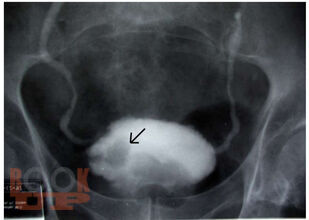

Учебное пособие содержит современную характеристику факторов риска развития рака мочевого пузыря (РМП), что позволит из общей массы амбулаторно-поликлинического приёма более чётко выделять тех пациентов, у которых имеется высокий риск развития онкопатологии. Рассмотрены важные клинические симптомы различных вариантов РМП, методы диагностики, лечения и профилактики, направленные на повышение онкологической настороженности среди врачей и населения. Предложенные авторами алгоритмы обследования больных в амбулаторном звене при первичном обращении пациента подчинены единой концепции и дают возможность индивидуализировать, упорядочить и контролировать работу по своевременной диагностике раковых заболеваний.